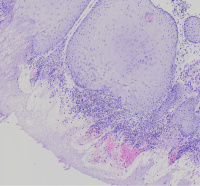

外阴多发赘生物,请教老师们,怎么报告?

性别

女

年龄

62

临床诊断

一般病史

发现外阴数十粒丘疹样结节,伴溃疡

标本名称

外阴丘疹样赘生物

大体所见

灰白色组织两粒0.5*0.3cm

考虑:疱疹病毒感染

疱疹性皮炎。

符合疱疹性皮炎。